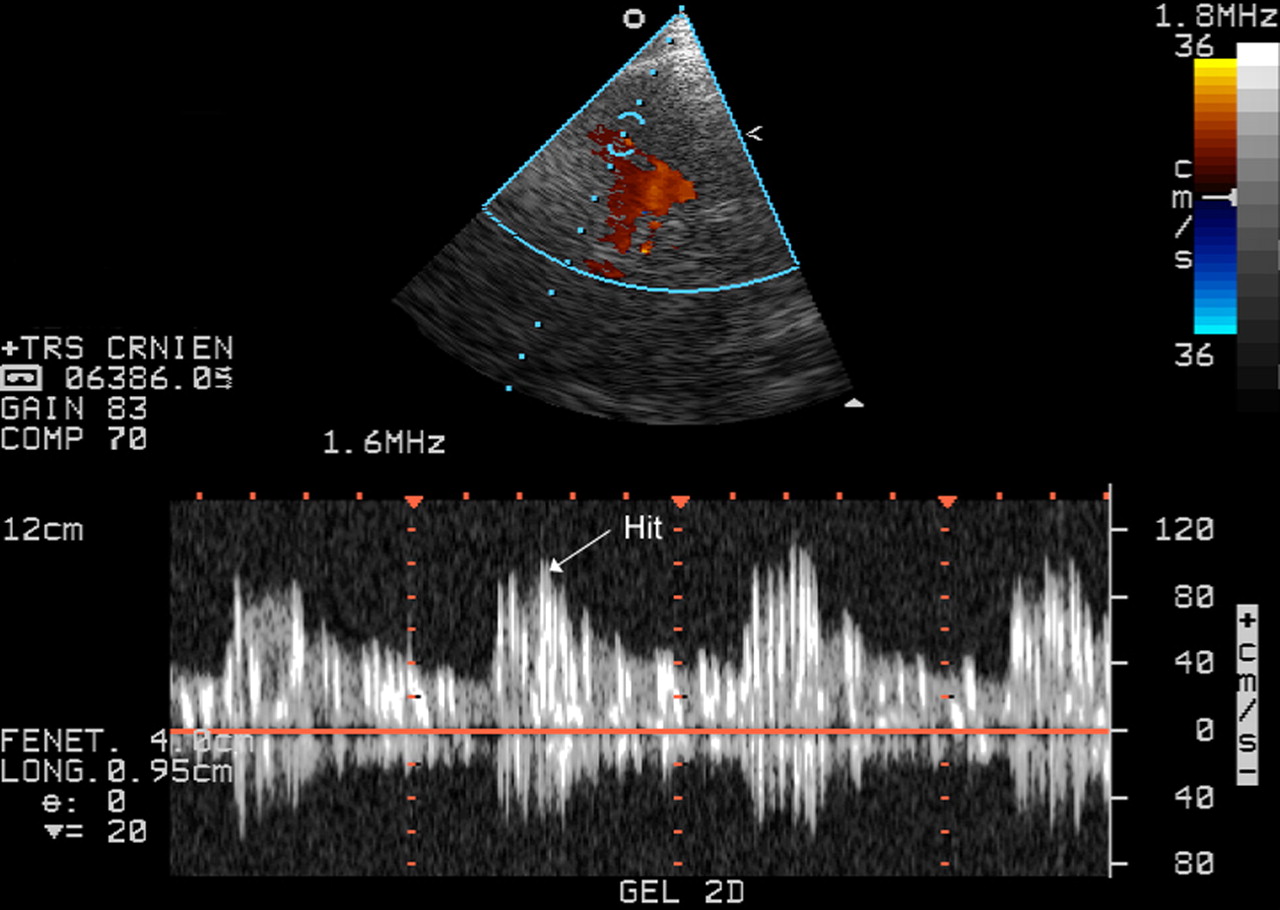

هفتبرکه (گریشنا): کلینیک پیشگیری از سرطان بیمارستان امیرالمومنین علی (ع) گراش مجهز به دستگاه TCD شد. به گزارش روابط عمومی دانشکدهی علوم پزشکی شهرستان گراش؛ امکان بررسی عروق داخل مغز، شریانهای گردن و بررسی علل سکته مغزی از قابلیتهای این دستگاه است. دکتر سید علیرضا موسوی، متخصص مغز و اعصاب و ستون فقرات، در مورد […]